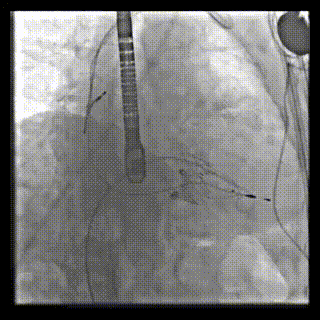

2021年12月24日,復(fù)旦大學(xué)附屬中山醫(yī)院葛均波院士團(tuán)隊成功應(yīng)用LuX-Valve Plus為一例極重度三尖瓣反流(TR)合并房顫、房缺的患者完成了經(jīng)血管三尖瓣置換術(shù),這是在前基礎(chǔ)上,本周完成的第三例經(jīng)血管三尖瓣置換手術(shù),葛均波院士、周達(dá)新教授等與心外科魏來教授、賴顥教授,心超室的潘翠珍教授、李偉教授及麻醉科的郭克芳教授共同完成了本周手術(shù),均獲得圓滿成功!患者術(shù)后超聲顯示無TR,臨床癥狀明顯改善。本周手術(shù)的成功也為LuX-Valve Plus救治性臨床研究添上了濃墨重彩的一筆。

本周三例接受LuX-Valve Plus經(jīng)血管三尖瓣置換術(shù)的患者中,第一例患者為冠狀動脈旁路移植術(shù)+Bentall+二尖瓣成形術(shù)后;第二例患者為永久起搏器植入術(shù)后,存在跨三尖瓣導(dǎo)線;第三例患者合并房顫、房缺及左心耳封堵術(shù)后。

三例患者入院后,葛均波院士團(tuán)隊周達(dá)新教授、潘文志教授、張源博士、陳莎莎博士及心超室的潘翠珍教授、李偉教授對患者的情況進(jìn)行詳細(xì)評估和討論,最終決定為三例患者選擇LuX-Valve Plus40mm、50mm和50mm型號的瓣膜進(jìn)行手術(shù)治療。手術(shù)后即刻拔除氣管插管,術(shù)后患者三尖瓣反流癥狀得到顯著改善,復(fù)查心超結(jié)果顯示人工三尖瓣瓣膜支架固定穩(wěn)定,瓣葉關(guān)閉形態(tài)未見異常,未見明顯反流。

LuX-Valve Plus是LuX-Valve系列產(chǎn)品的第二代,采用的是經(jīng)血管入路的全新輸送系統(tǒng),其設(shè)計開發(fā)過程得到了上海中山醫(yī)院葛均波院士及其團(tuán)隊的精心指導(dǎo),研究結(jié)果提示瓣膜植入的安全性和有效性俱佳,尤其瓣膜獨特的設(shè)計使其具有極佳自適應(yīng)性,本周三例患者病因及解剖結(jié)構(gòu)各具特點,但均可從LuX-Valve Plus植入術(shù)明顯獲益。目前,LuX-Valve Plus已在全國各中心開展救治性臨床研究,相信未來定會為更多的三尖瓣反流患者帶來福音。